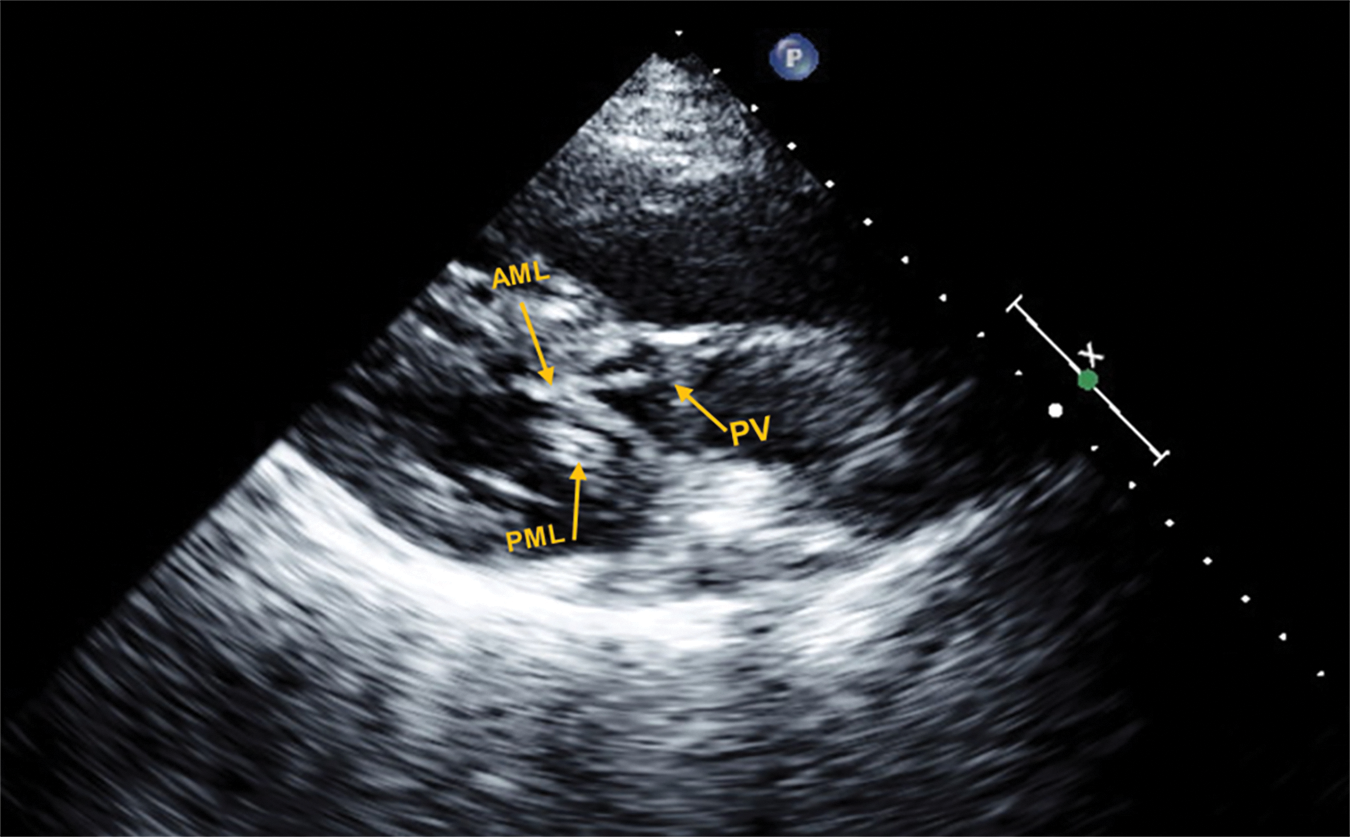

Figure 2: Representative echocardiogram in the parasternal long axis view, of a patient with d-TGA/AtS and SAM with LVOTO

In this frame, both the PML and AML are elongated and show bileaflet SAM with complete obstruction of blood flow through the PV during mid to late ventricular systole; pressure gradient measured at 110 mmHg.